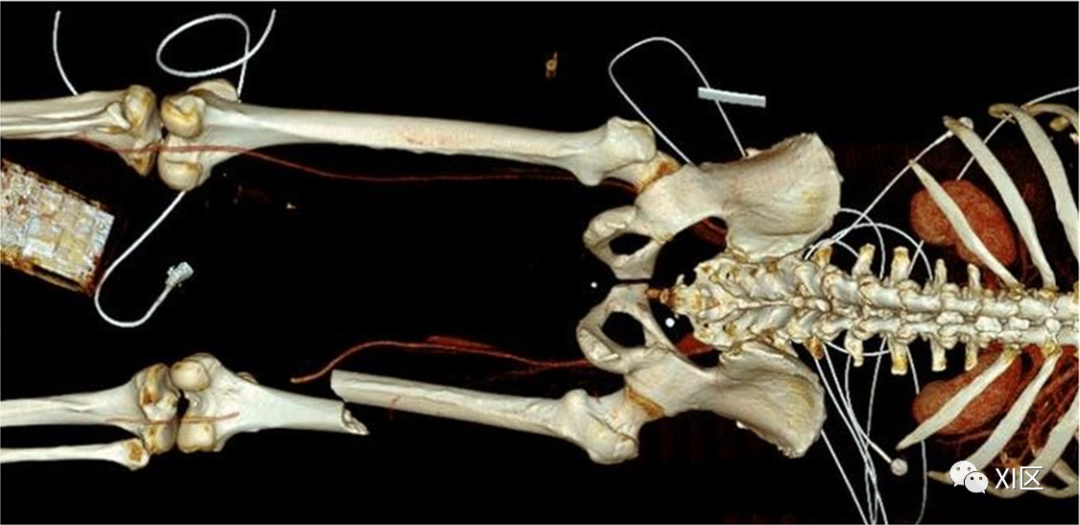

图9 创伤后血管截断。36岁的摩托车事故患者的CTA。容积渲染3D重建显示右股浅动脉和腘动脉之间通道处的血管截断。

剥离表现为内膜层损伤的影响,在CTA上可以观察到一种薄的线性腔内填充缺陷(图10)。

图10 医源性夹层。82岁女性患者的CTA,她在前一天接受了经皮腔内血管成形术。右侧冠状MPR重建、CPR重建和轴位腔内可视化显示左侧股浅动脉夹层的典型外观,在血管腔内可见线性皮瓣。

夹层会增加血管血栓形成或扩散到外膜层的风险,导致夹层动脉瘤的发生。局部管腔狭窄(图11)可以是固定的,与狭窄有关,也可以是可逆的,如痉挛。